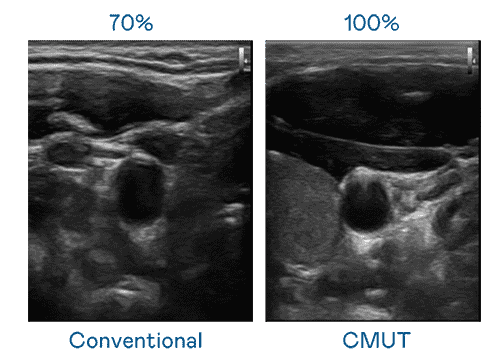

CMUT 技术是一种用电容式微机电元件来产生超音波讯号的技术。。与传统 PZT 压电式技术相比,,,CMUT 频宽增加 30%,,更宽频的超音波讯号让影像解析度大幅提升,,,是实现高影像品质医疗超音波扫描、、促进精准医疗发展的关键技术。。。

大频宽带来超清晰影像

超音波影像的解析度高低,,,首先取决于探头能发出的讯号频宽。。。。森林舞会 CMUT 可提供高清晰的超音波讯号,,,提供高频宽、、、、高灵敏度、、影像纹理细节更高的超音波影像,,,,协助医护人员缩短影像判读时间及利用精准的医疗影像进行诊断。。。。